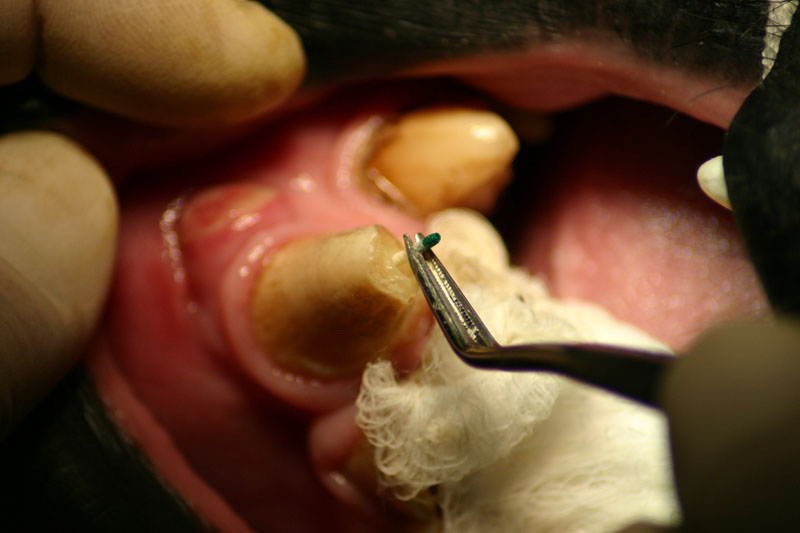

An 18 month old, 7.5 kg , female caracal (Caracal caracal caracal) new to the Milwaukee County zoo collection presented with a fractured right maxillary canine tooth during routine quarantine examination. The canine tooth had approximately 3 mm of its tip fractured off, the pulp chamber was exposed, and the tooth was darkened due to degeneration of of the pulpal tissue, and induction of food debris. There was no sign of an external drainage tract lesion. Radiographic examination revealed the presence of a periapical lesion 6mm by 7mm in diameter. The extra-oral surgical approach was chosen to debride the periapical lesion, resect the apex, and perform a retrograde fill in conjunction with the coronal or oblique endodontic fill.

A horizontal incision was made rostral to the medial canthus of the eye, dissecting to bone. The patients' eyes were draped for protection. A 558 surgical bur in a water cooled high speed dental handpiece was used to cut through the bone and expose the canine apex and lesion.